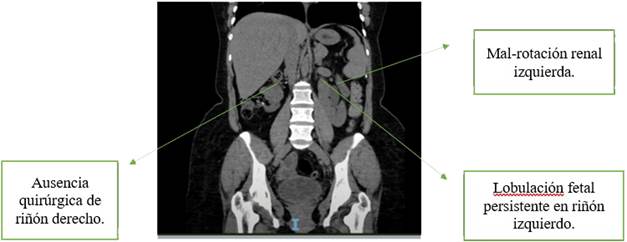

Se practica uroanálisis que evidencia esterasa leucocitaria y nitritos positivos, bacterias en sedimento; gram con bacilos gram negativos y urocultivo con E. coli. Se practica tomografía simple (UROTAC) que evidencia nefromegalia, malrotación izquierda y posible anomalía de fusión, dada su condición de monorrena se practica uroresonancia que confirma nefromegalia, malrotación, lobulación fetal persistente izquierda y ausencia quirúrgica de riñón derecho (Figuras 1 y 2).

Avances en imágenes diagnósticas han permitido clasificar las CAKUT. Sin embargo en este artículo hablaremos con más profundidad de la lobulación fetal persistente que es la presencia de pequeñas hendiduras separadas por surcos entre las pirámides renales. Se presenta en el 4% de la población adulta.

Estas lobulaciones se mantienen durante el periodo fetal pues son indicador importante del desarrollo del feto y se hacen imperceptibles en el tercer trimestre para transformarse en una superficie lisa.6 Esta se deriva de la persistencia durante toda la adultez de una de las doce lobulaciones fetales.7 Se identifica por imágenes como la ecografía de vías urinarias. Estas lobulaciones están en el 8% de riñones derechos, 12% de riñones izquierdos y el resto en ambos riñones de quien las padece.8

También se identifican por imágenes como UROTAC o uroresonancia. Sin embargo, es clave recordar que la lobulación fetal persistente es un hallazgo fortuito en diversos procesos diagnósticos. No causan ninguna afectación a la vida cotidiana por sí mismas, pero su detección alerta sobre la posibilidad de otras CAKUT que si causan complicaciones graves; en este caso hidronefrosis con pérdida renal.

Por otro lado, la paciente tiene asociada malrotación, que es una malformación con una posición anormal con respecto al hilio, característicamente encontramos uréter lateralizado y un hilio anterior con respecto a su posición normal. Puede ser bilateral o unilateral y suele ser hallazgo fortuito. Como hallazgo aislado no tiene relevancia clínica y es asintomática; por lo cual tenemos datos en 1 de cada 2000 autopsias.